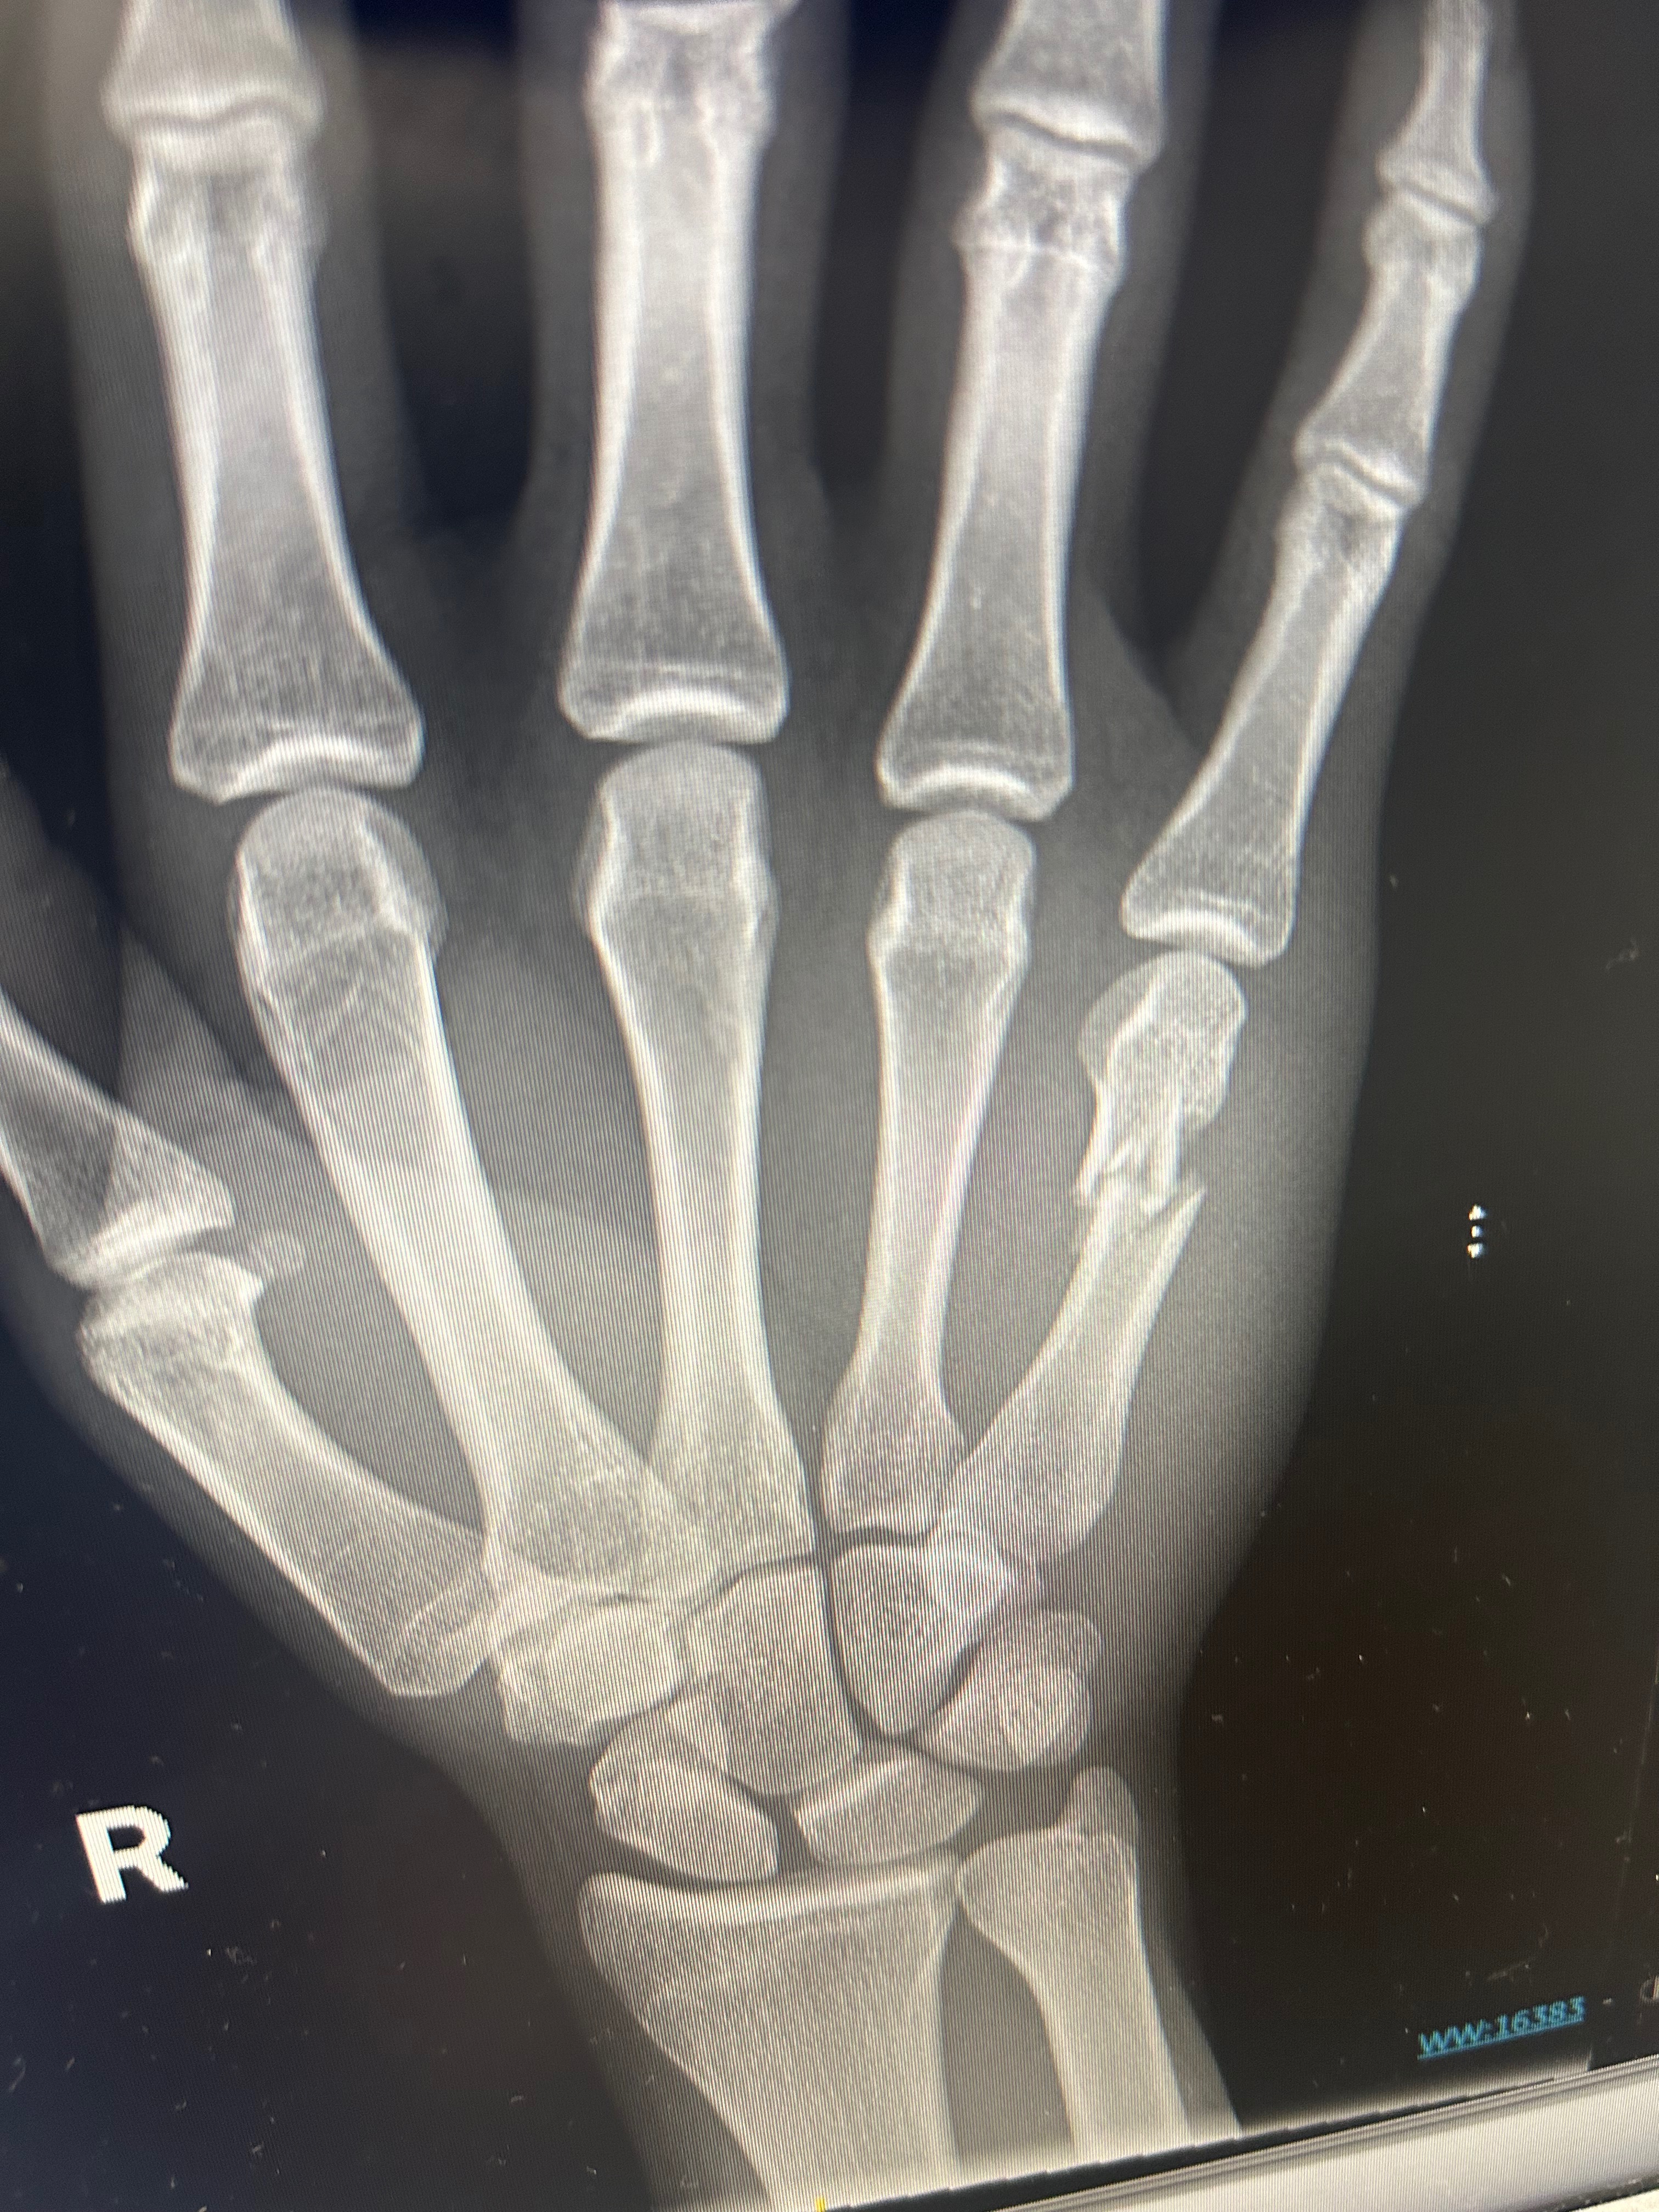

Two weeks ago I broke my hand and the following week I found out that the bone I broke is now shifting and I am in need of surgery. Or it will not heal right

In order to go to the military. I need to have surgery and be medically cleared if I do not get the surgery, the military is out though question because they are saying that it will heal wrong and I won’t have full motion in my hands, nor will I be able to grip things properly.